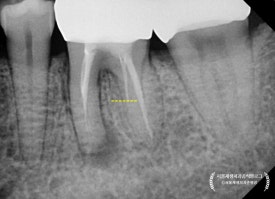

곧이어 치근단엑스레이를 찍어보았지요.

어금니는 뿌리가 여러개기 때문에, 경우에 따라 각도를 달리하여

2장 이상 촬영하기도 한답니다.

통상 아래 어금니에는 신경이 4개 (적으면 3개, 많으면 5개) 있게 마련이죠.

그런데 조금 이상합니다.

4개 중에 2개가 뿌리 전체 길이에 못미치게 치료가 되어 있습니다.

현미경을 이용해서

뿌리 끝까지 청소를 해 내려간 결과,

노랗고 빨간 고름이 뿌리 끝에서 퐁퐁퐁 솟아나는 것을 관찰할 수 있었습니다.

딱딱한 뼈 안에 고름이 차오르고 있었으니

얼마나 아팠을까요?